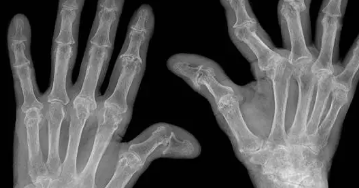

류마티스 관절염의 특징적인 증상은 손과 발의 작은 관절에서 좌우 대칭적으로 관절염이 생기는 것입니다.

혈액검사와 엑스레이로 진단합니다.